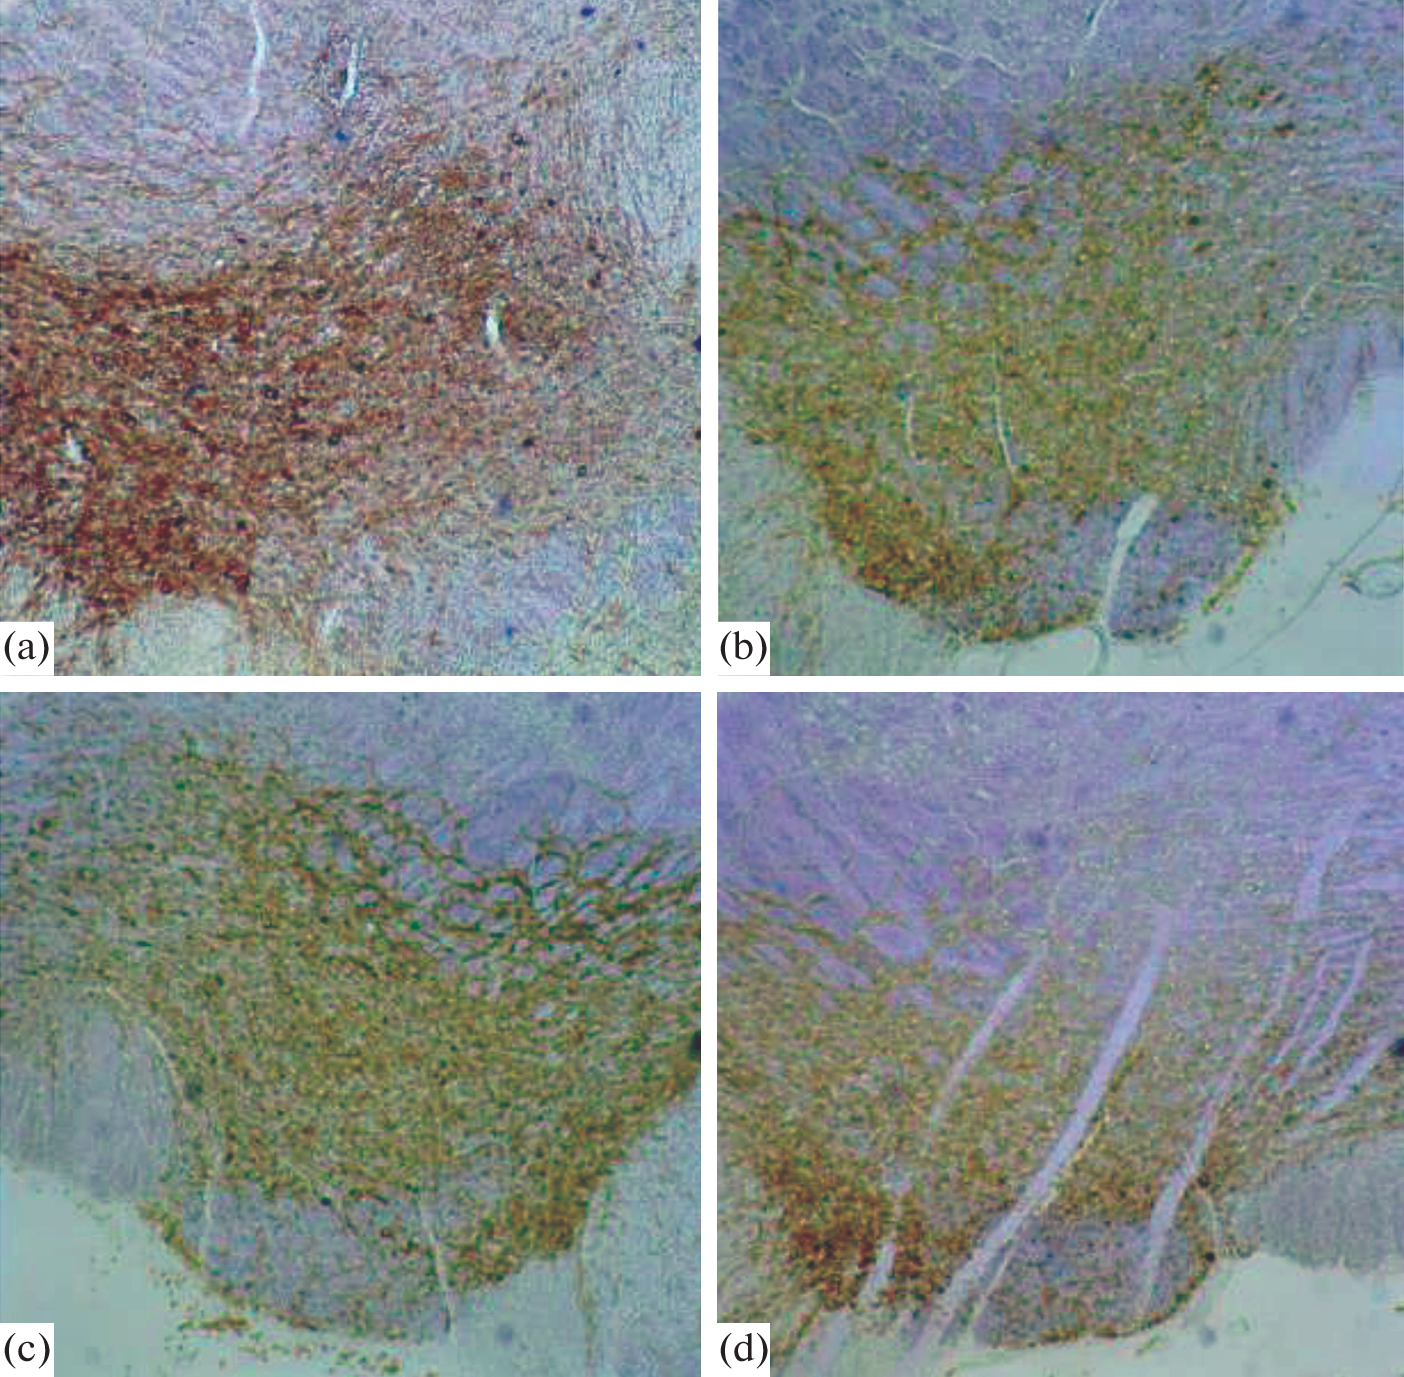

Крысы линии WAG/Rij являются генетической моделью абсанс-эпилепсии с коморбидной депрессией. Показано, что патологический фенотип у крыс линии WAG/Rij связан с пониженным дофаминовым (ДА) тонусом в мезолимбической системе мозга. Ранее было обнаружено, что материнская метилобогащенная диета (МОД) в перинатальном периоде повышает содержание ДА в мезолимбической ДА-ергической системе мозга и уменьшает проявление абсанс-эпилепсии и коморбидной депрессии у взрослого потомства крыс линии WAG/Rij. Вентральная тегментальная область (ventral tegmental area, VTA), содержащая тела ДА-ергических клеток, является главным источником синтеза мезолимбического ДА. Цель настоящей работы – проверить гипотезу о том, что повышение ДА-ергического тонуса мезолимбической системы мозга, вызываемое материнской МОД у потомства, может быть обусловлено увеличением числа ДА-ергических нейронов, активно синтезирующих тирозингидроксилазу (TH) в VTA, которая является началом мезокортикального и мезолимбического ДА-ергических путей. Использовали метод иммуногистохимического окрашивания на TH для оценки числа TH-иммунопозитивных клеток у взрослого потомства крыс линии WAG/Rij, рожденного матерями, потреблявшими контрольную диету или МОД, и подвергнутых и не подвергнутых поведенческому тестированию в течение 2 дней подряд в тестах свето-темнового выбора, открытого поля, приподнятого крестообразного лабиринта и вынужденного плавания. Через 1 ч после теста вынужденного плавания была проведена транскардиальная перфузия с целью фиксации головного мозга. Число ДА-ергических нейронов определяли по числу TH-иммунопозитивных клеток на срезах мозга на уровне VTA. Число TH-иммунопозитивных клеток подсчитывали в левом и правом полушариях мозга в отдельности. Установлен значимый эффект МОД матери на число клеток в VTA, экспрессирующих TH. У взрослого потомства крыс линии WAG/Rij, рожденного матерями, потреблявшими МОД, число TH-иммунопозитивных клеток было больше по сравнению с потомством крыс линии WAG/Rij, рожденного матерями, потреблявшими контрольную диету. Кроме того, у потомства крыс, рожденного матерями, потреблявшими МОД, число TH-иммунопозитивных клеток было больше у животных, подвергнутых поведенческому тестированию, по сравнению с животными, которых не подвергали поведенческому тестированию. Эффект материнской диеты и поведенческого тестирования на число TH-иммунопозитивных клеток в VTA был выражен одинаково в правом и левом полушариях мозга. Результаты свидетельствуют о том, что материнская диета в перинатальном периоде может влиять на развитие мезолимбической ДА-ергической системы мозга, способствуя образованию и/или сохранности ДА-ергических нейронов в VTA, и тем самым предотвращать возникновение генетической абсанс-эпилепсии и коморбидной депрессии у потомства крыс линии WAG/Rij.